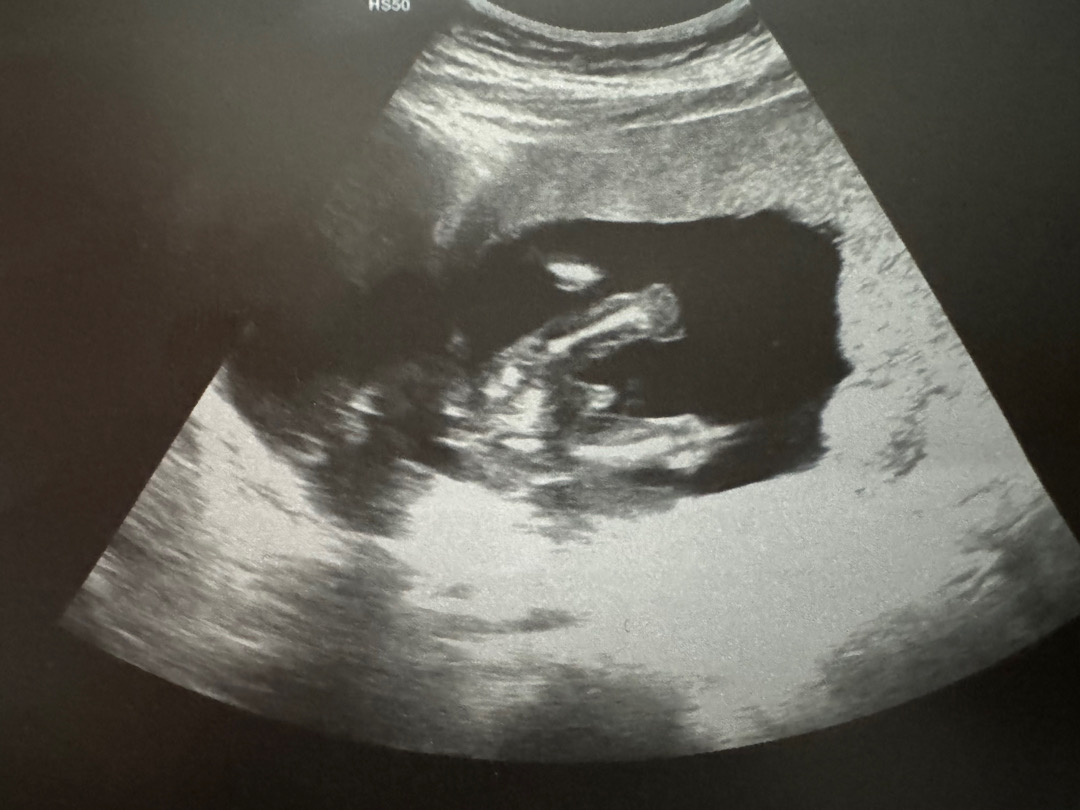

16주차 초음파사진인데 100%아들인가요?

주변에서 다들딸같다라고말을많이들었는데..아들인가요?

근데 병원서 얘기안해주시나요? 저는 저번주에 16주차였는데 얘기해주셨거든요

보이네요. 80퍼센트입니다라고하셨어요

넹 🌶️존재감이 뿜뿜하네용ㅋㅋㅋㅋ

네 아들이네요ㅎㅎ